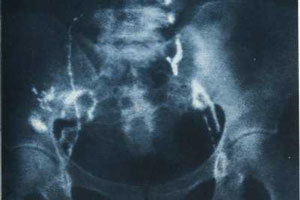

При четвертой стадии новообразование распространяется за пределы малого таза и начинает внедряться в кишечник и мочевой пузырь. На данном этапе распространяются метастазы, которые поражают соседние органы и распространяются в легкие.

На фото можно видеть, что на последней стадии патологический процесс переходит с шейки матки за границы малого таза и поражает кишечник и мочевой пузырь.

Кроме этого, отмечается появление метастаз, то есть опухоль внедряется в отдаленные органы и ткани. Заключительная фаза рака считается самой сложной и опасной, и выживаемость женщин в последующие несколько лет довольно низкая.

Сколько живут с раком шейки матки 4 стадии и есть ли шансы?Прорастание в соседние органы

Рак шейки матки 4 стадии

Опухоль

стремительно распространяется, поглощая близлежащие ткани и захватывая новые отдаленные

территории. Рак шейки матки 4 стадии – это практически всегда наличие

метастатического поражения. Карцинома последней степени развития разделяется на

следующие варианты:

• Опухоль

покидает границы костного таза, добираясь до слизистых оболочек соседних

органов (мочевой пузырь, мочеточники, прямая кишка);

• Прорастание

внутрь смежных органов;

• Наличие

отдаленных метастазов.